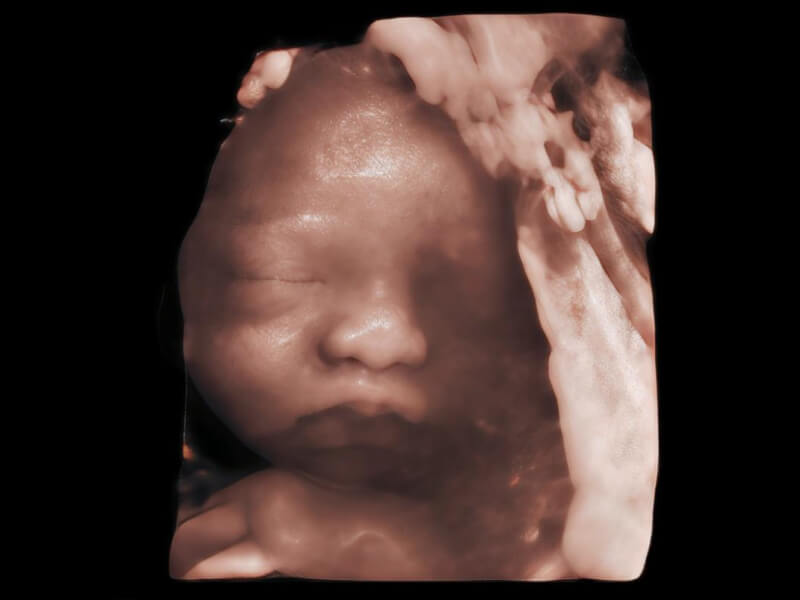

夢(mèng)溪?P80以“關(guān)愛女性”為基石,提供全方位的解決方案,量身定制以滿足女性的健康需求,涵蓋婦科、生殖健康檢查、產(chǎn)前篩查及產(chǎn)后康復(fù)等領(lǐng)域。